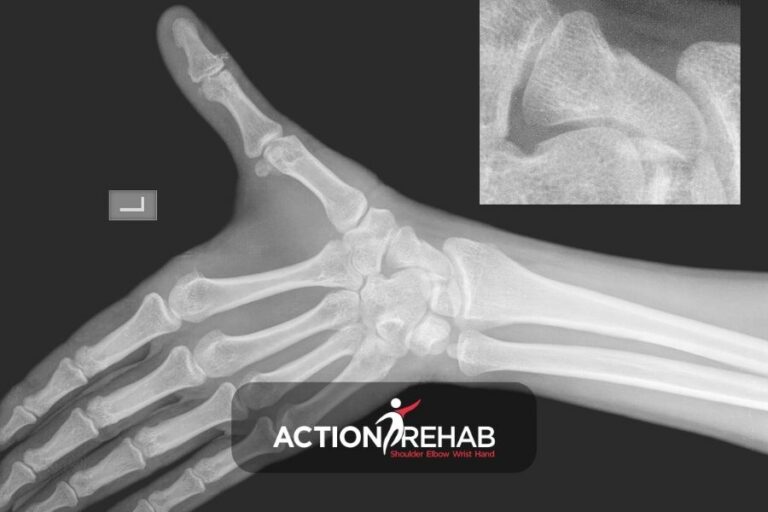

Osteoporosis is a condition that affects millions of Australians, particularly women over the age of 50. At Action Rehab we often treat patients with wrist fractures resulting from osteoporosis. In this article, we’ll explore the connection between wrist fractures and osteoporosis, as well as preventative measures and treatment options. What is Osteoporosis? Osteoporosis is…